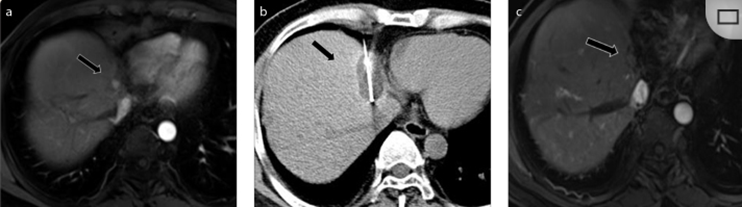

79 歲男性,肝轉(zhuǎn)移(結(jié)直腸癌)腫瘤的完全消融病例

( a ) 軸向 MRI 和 ( b ) 軸向 CT 顯示肝S8段有一個16mm的病灶,鄰近肝緣。( c )冷凍消融期間CT顯示放置了2個冷凍探針,低密度冰球包圍病灶。(d)術(shù)后1個月隨訪 CT顯示冰球?qū)?yīng)的壞死區(qū)域,未見復發(fā)。(e)術(shù)后6個月的CT,壞死區(qū)域縮小,未見復發(fā)。(f)與基線影像(g)相比,12個月后的FDG-PET/CT顯示未見FDG攝取。

62歲女性,肝轉(zhuǎn)移(卵巢癌)腫瘤的完全消融病例(a)軸向CT顯示病變位置毗鄰心臟和上腔靜脈(黑色箭頭)。(b)術(shù)中軸向CT掃描:使用三個冷凍探針。1個月后的軸向(e)和冠狀位(f)增強CT掃描顯示低密度區(qū)域,由于肉芽組織反應(yīng)引起的邊緣增強。